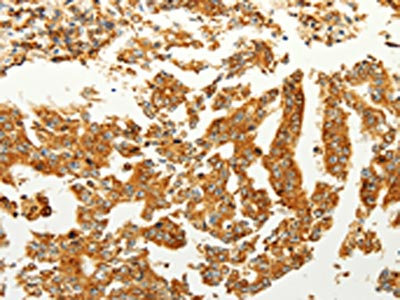

The image on the left is immunohistochemistry of paraffin-embedded Human thyroid cancer tissue using CSB-PA032335(FZD6 Antibody) at dilution 1/60, on the right is treated with synthetic peptide. (Original magnification: ×200)

The image on the left is immunohistochemistry of paraffin-embedded Human gastric cancer tissue using CSB-PA032335(FZD6 Antibody) at dilution 1/60, on the right is treated with synthetic peptide. (Original magnification: ×200)